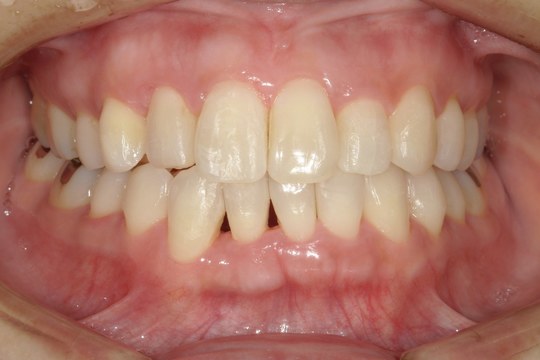

M.I. 40代女性

上下の前歯をキレイに並べたい、中心がズレている、という主訴でご来院。上下前歯の叢生を治し、正中を合わせました。

治療の期間:R3. 4/13〜R5. 8/30

治療の価格:88万円